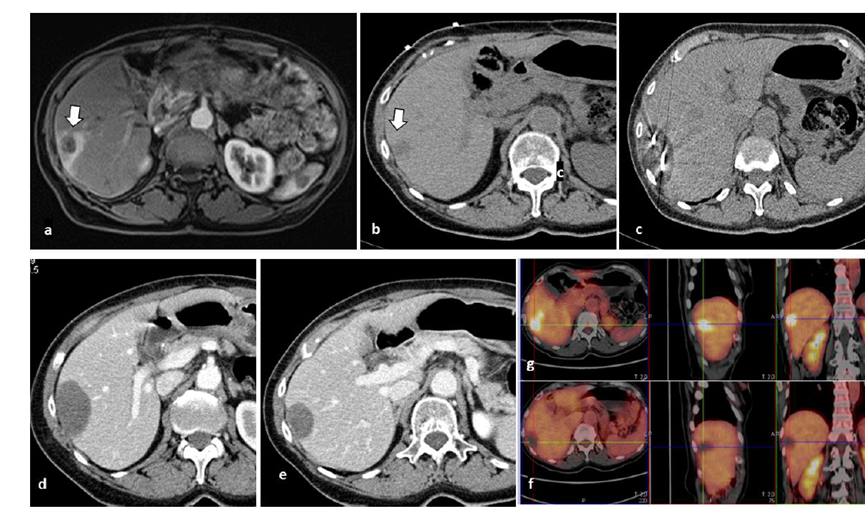

79 歲男性,肝轉移(結直腸癌)腫瘤的完全消融病例

( a ) 軸向 MRI 和 ( b ) 軸向 CT 顯示肝S8段有一個16mm的病灶,鄰近肝緣。( c )冷凍消融期間CT顯示放置了2個冷凍探針,低密度冰球包圍病灶。(d)術后1個月隨訪 CT顯示冰球對應的壞死區域,未見復發。(f)與基線影像(g)相比,12個月后的FDG-PET/CT顯示未見FDG攝取。

(a)軸向CT顯示病變位置毗鄰心臟和上腔靜脈(黑色箭頭)。1個月后的軸向(e)和冠狀位(f)增強CT掃描顯示低密度區域,由于肉芽組織反應引起的邊緣增強。